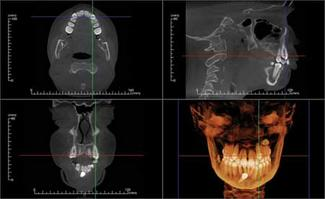

Dolphin Imaging® (dolphinimaging.com) and InVivoDental by Anatomage® (www.anatomage.com) are two software developers who are on the cutting edge of software for orthodontic and orthognathic treatment-planning and archiving. Both packages offer conventional cephalometric analysis based upon digitized 3-D volume renderings. The soft tissue and facial photos (in 2-D or stereographic formats via 3-D MD camera system) can be superimposed and phased in over the skeleton with a translucency feature. This feature enables integrated dento-facial analysis showing how the soft tissues are influenced by dento-skeletal positions. Location, size, and density of lesions and bone cysts — as well as positions impacted and supernumerary teeth — can be rendered in 2-D and 3-D to help determine the best approach for surgical access. (Figure 2).